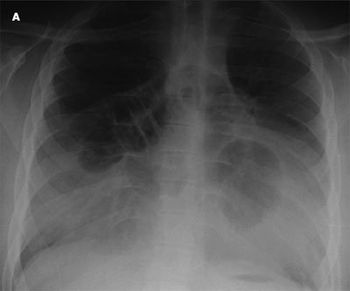

A 5-year-old boy with a history of allergies and asthma presents with fever (temperature of 40°C [104°F]), headache, cough, vomiting, and diffuse pain in and around the chest area on the right side. The patient has never traveled and has no sick contacts. A chest radiograph is obtained (A).